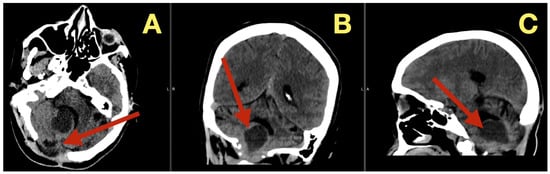

CT scans completed on the first post-operative day (Figure 3) were utilized to exclude hemorrhage and assess early ventricular diameter; they indicated posterior fossa re-expansion, full reopening of the fourth ventricle, normal brainstem convexity, and no early hydrocephalus. A second CT scan completed 7 days post-operatively (Figure 4) verified stable ventricular and outlet patency and excluded late onset hydrocephalus. The one month follow-up CT scan (Figure 5) provided a baseline for long-term comparisons. Later surveillance relied upon MRI including DWI to exclude diffusion-positive residual or recurrence.

Figure 3. Immediate postoperative CT scan. (A): Axial CT showing full decompression of the fourth ventricle and restoration of normal CSF circulation (arrow). (B): Coronal CT demonstrating complete midline re-expansion with absence of residual mass (arrow). (C): Sagittal CT confirming brainstem relaxation and normalization of posterior-fossa anatomy (arrow).